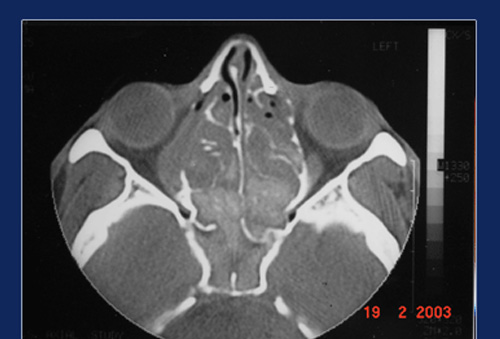

ACUTE MUCORMYCOSIS

Mucor is an opportunistic fungus present as a commensal in the throat and nose of normal individuals. In diabetics and immuno compromised individuals the mucor becomes pathological to produce an acute sinusitis with tissue destruction. Maxillary sinus is commonly affected, typically with whitish mucopus and bone destruction. The adjacent sinus walls are eroded and CT shows bone demineralisation and pathological fracture of sinus walls. The treatment is Endoscopic debridement and control of diabetes. Usually the sinus returns to normal even without antifungal treatment. Many sittings of debridement may be required and sometimes abscess formation may occur in the pterygopalatine or infra temporal fossae which has to be drained. On the whole, it carries good prognosis if treatment is started early.